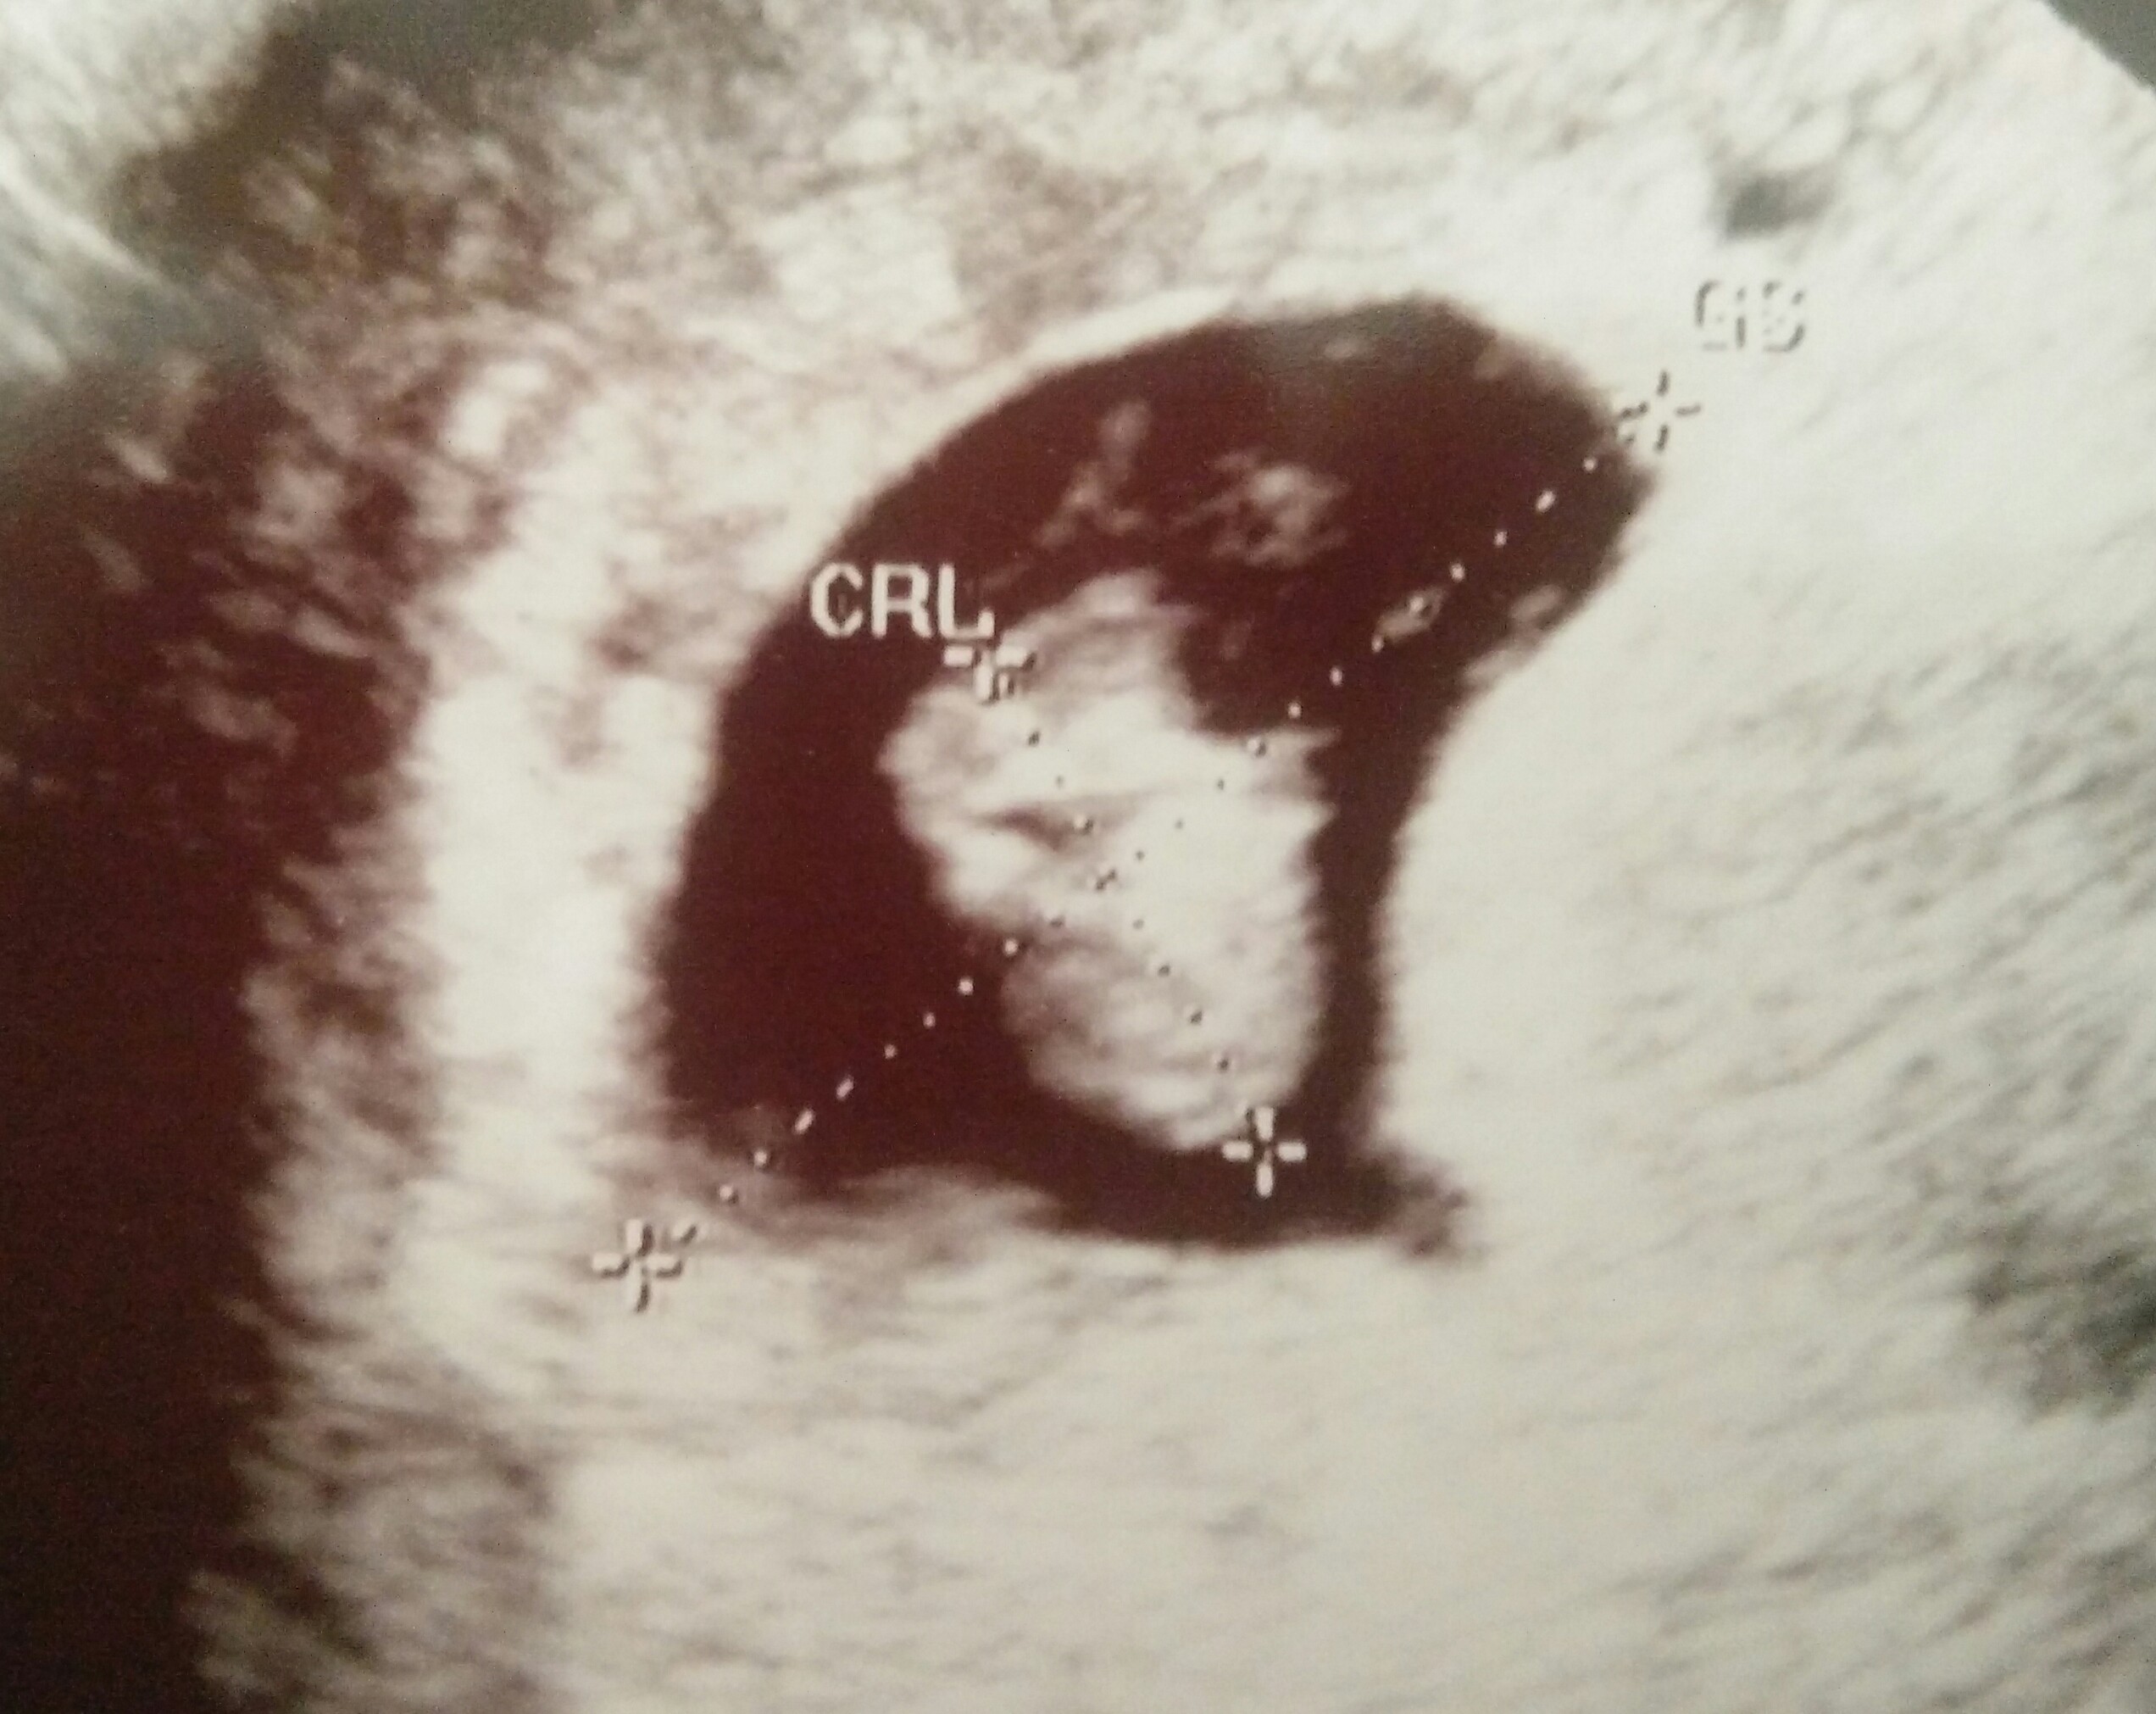

GratulujęO rany, aż się wzruszyłam! Serducho pięknie bije, wszystko superdzidzio ma 1,1cm, 7 tyg1dzien, termin wg usg na 09/06

[emoji7] [emoji7] [emoji7]O rany, aż się wzruszyłam! Serducho pięknie bije, wszystko super [emoji173]️dzidzio ma 1,1cm, 7 tyg1dzien, termin wg usg na 09/06